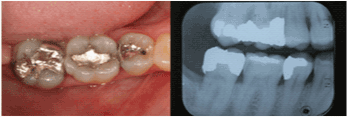

| Mandibular Right Second

Molar |

11 |

43.8% |